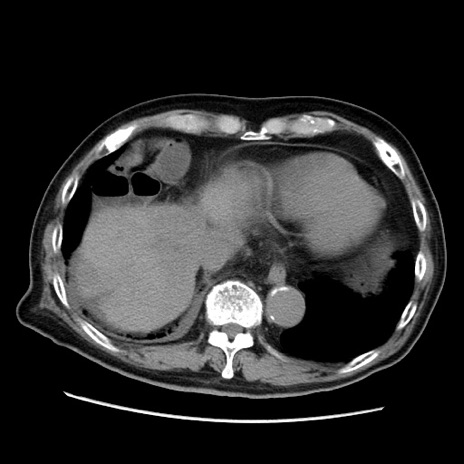

症例21(横断像)

【症例】70歳代男性

【主訴】腹痛

【現病歴】肝硬変・肝細胞癌にてかかりつけの方。約9時間前に食後より腹痛出現。症状が徐々に増悪し、嘔吐出現したため来院。

【既往歴】肝硬変、肝細胞癌(RFA、TACE後)

【身体所見】意識清明、表情苦悶様、BT 36℃、BP 129/78mmHg、P 88bpm、SpO2 97%(RA)、右上腹部から心窩部にかけて圧痛あり、反跳痛なし、筋性防御あり。

【データ】WBC 5800、CRP 0.16

冠状断像